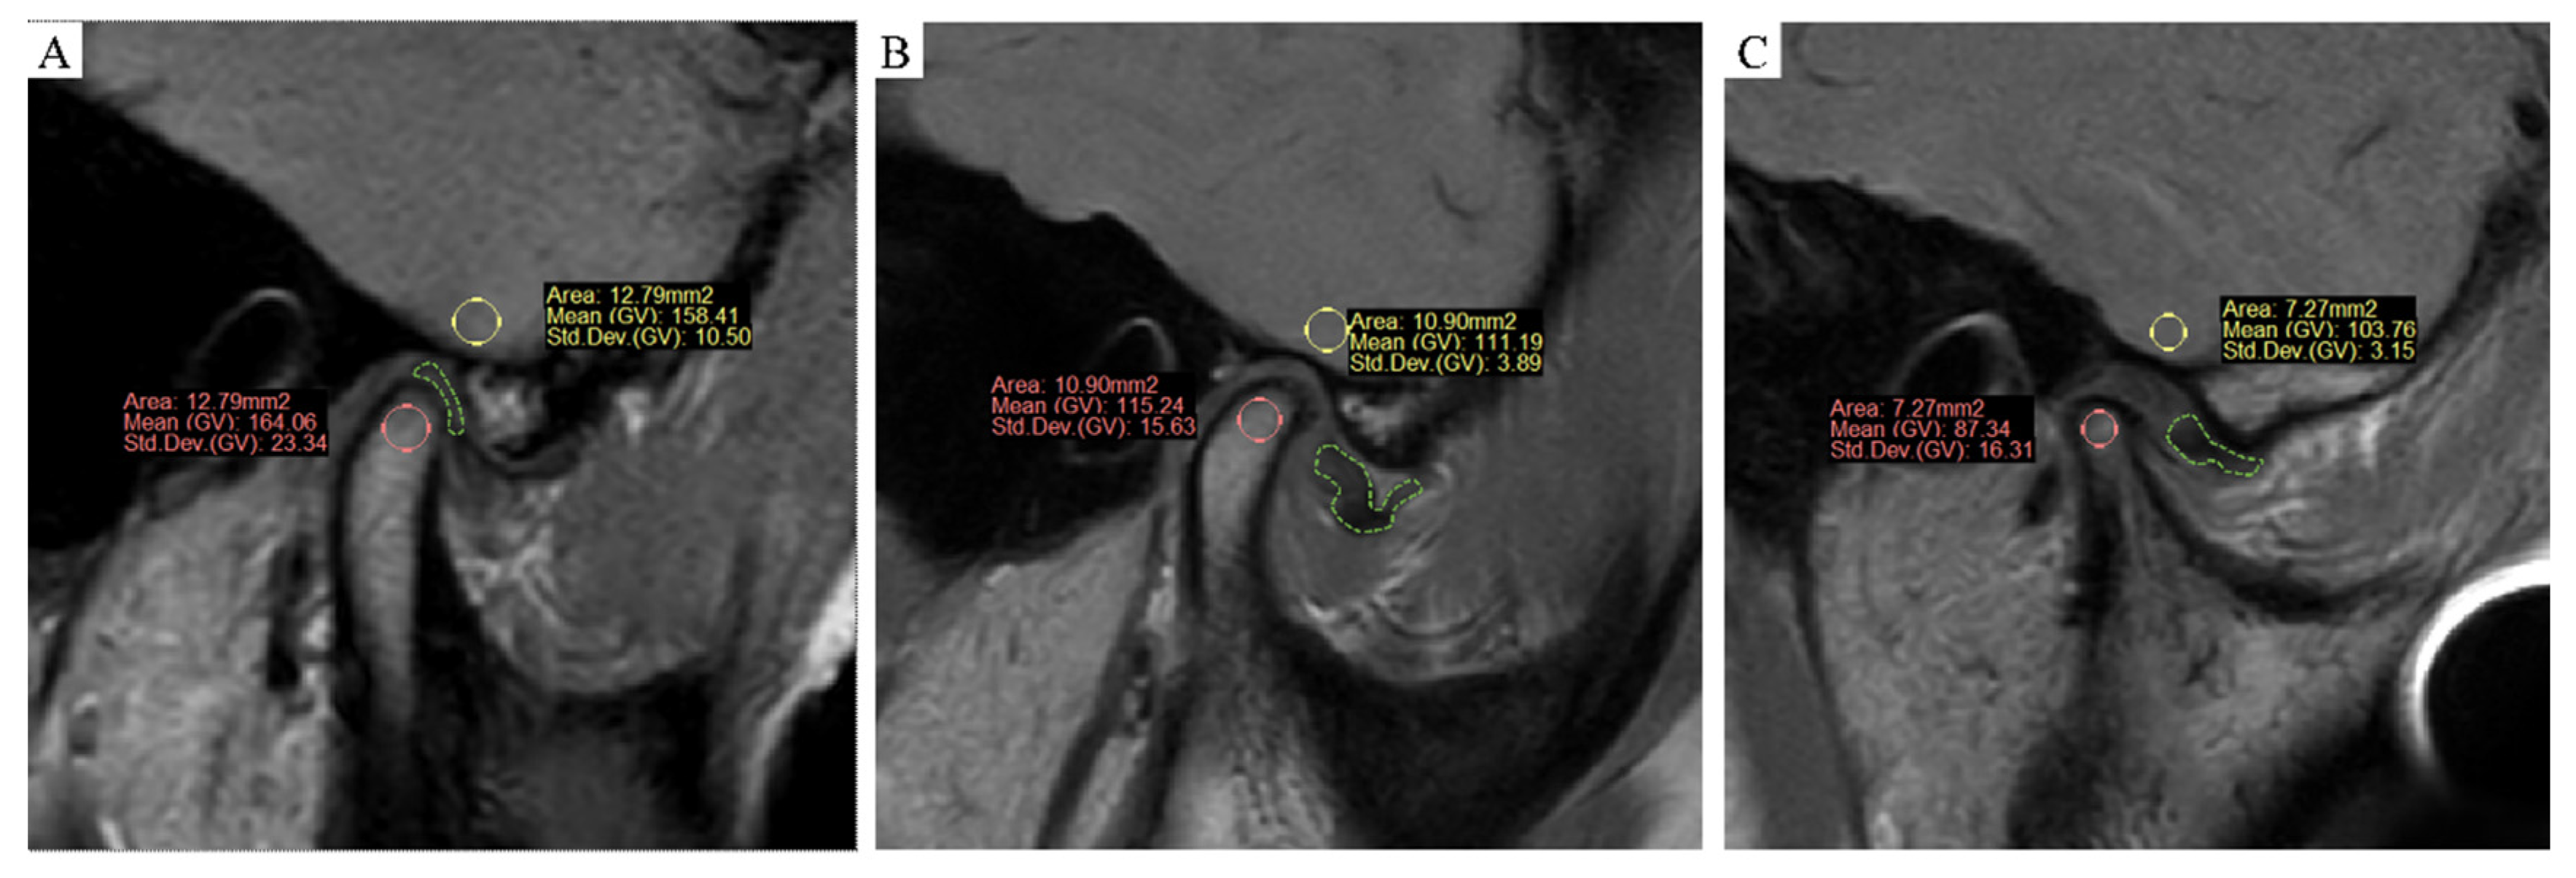

2.2. MRI

2.3. Measurements and Analysis